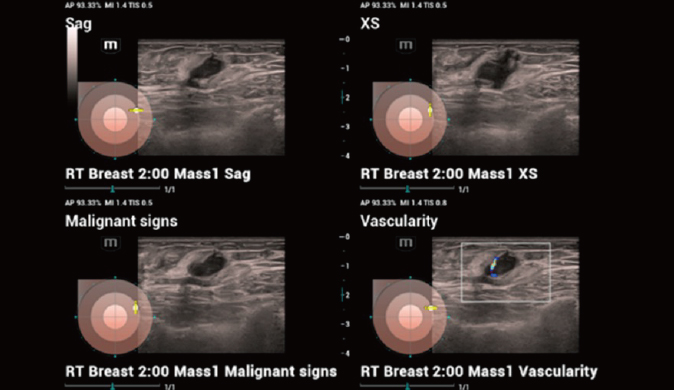

Für die Ultraschalltechnologie stellt die ZST+-Plattform einen bedeutenden Fortschritt dar, da sie statt der herkömmlichen Strahlformung die Kanaldatenverarbeitung verwendet. Diese bahnbrechende Innovation löst übliche Zielkonflikte zwischen räumlicher Auflösung, zeitlicher Auflösung und Homogenität des Gewebes auf, woraus sich eine beispiellose Bildqualität ergibt, die den Weg frei macht für unendlich viele Bildgebungslösungen.

Das Resona I8 weist vielfältige klinische Lösungen auf, die speziell für den jeweiligen Anwendungsbereich entwickelt wurden. Die Technologie baut auf einem tiefgreifenden Verständnis verschiedener klinischer Szenarien auf und bietet eine umfassende Serie fortschrittlicher Diagnoseinstrumente, beispiellose Intelligenz und präzise Analysen zur Verbesserung von Diagnosesicherheit, Qualitätskontrolle und Scaneffizienz.